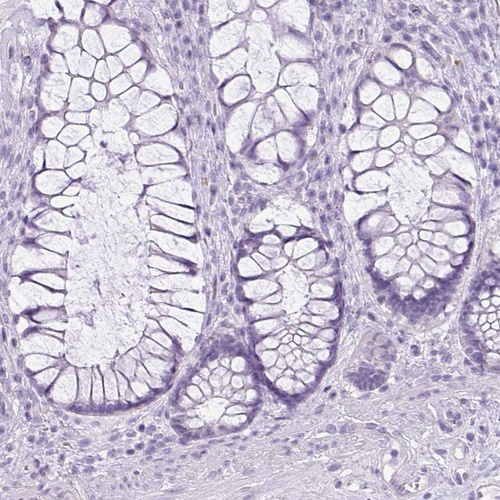

Immunohistochemistry analysis in human kidney and testis tissues using HPA036260 antibody. Corresponding CDH16 RNA-seq data are presented for the same tissues.